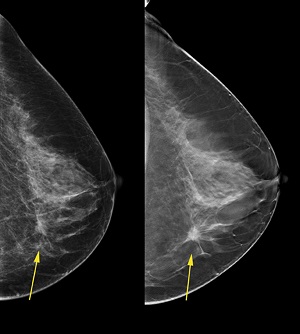

Three-dimensional mammography (also called digital breast tomosynthesis, digital tomosynthesis, or just tomosynthesis) creates a three-dimensional picture of the breast using X-rays. Several low-dose images from different angles around the breast are used to create the 3-D picture.

A conventional mammogram creates a two-dimensional image of the breast from two X-ray images of each breast.